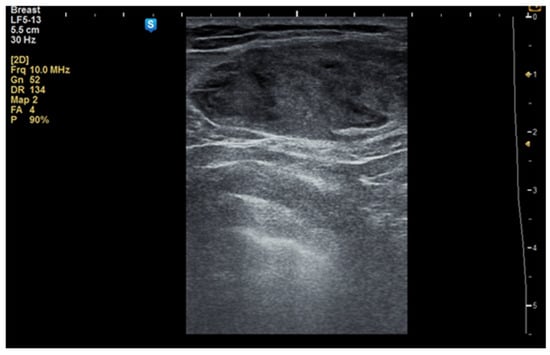

Although the literature identifies mammography as the primary diagnostic method for breast hamartomas, in our study, the diagnosis was established via ultrasound examination. This preference is due to the younger age of many patients, with only three being over 50 years old. On ultrasound, hamartomas typically appear as oval, well-circumscribed masses with heterogeneous hypoechoic or isoechoic echostructures and reduced or absent vascularity (Figure 1 and Figure 2). In our study, the concordance between ultrasound and histological size was 84.61%. Preoperative ultrasound diagnosis of hamartoma was established in only five patients, representing 38.46% of the cases.

Figure 1. Ultrasound image of a 34-year-old woman with a right breast hamartoma of 65/35 mm, with heterogeneous hypoechoic structure, located in the upper inner quadrant.